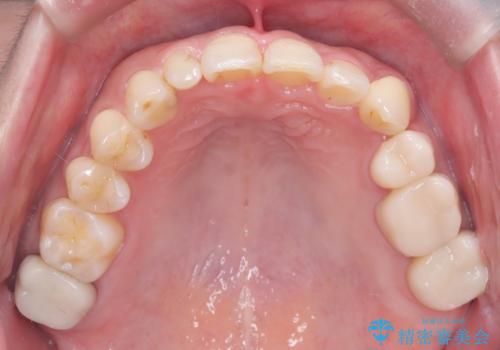

治療のポイントは、40代という節目に、将来的なメンテナンスのしやすさも考慮した機能的な歯並びを構築することでした。

まず、計画通り左上4番を抜歯し、そのスペースを利用して八重歯を徐々に正しい位置へと移動させました。ワイヤー矯正特有の「歯を細かく、確実に動かす力」を最大限に活用し、歯根の向きまで丁寧に調整。

治療が進むにつれ、突出していた八重歯がスムーズに列に収まり、凹凸がなくなったことで、以前よりもブラッシングがしやすく清潔な口腔環境が整いました。治療完了後、長年のコンプレックスから解放された患者様の笑顔は非常に明るく、40代からでも遅くない「大人の矯正」の大きなメリットを実感していただける症例となりました。